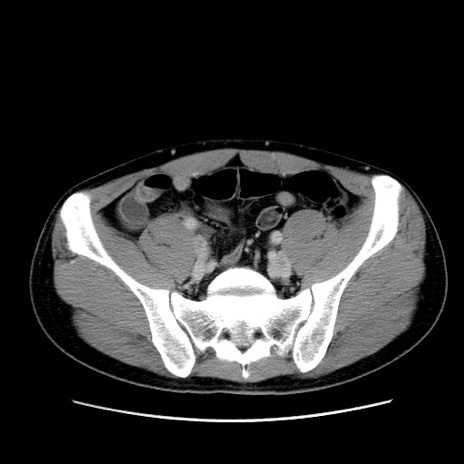

症例36(横断像)

【症例】20歳代 男性

【主訴】心窩部痛

【現病歴】今朝より上腹部痛あり。一旦軽快していたが再度出現したため救急要請。昨日夕に白身の魚を含む刺身を食べた。

【身体所見】BP 136/89mmHg、HR 74/min、BT 37.0℃、腹部:膨満、軟、心窩部に圧痛あり。反跳痛なし、筋性防御なし、腸雑音やや亢進あり。

【データ】WBC 17700、CRP 0.48